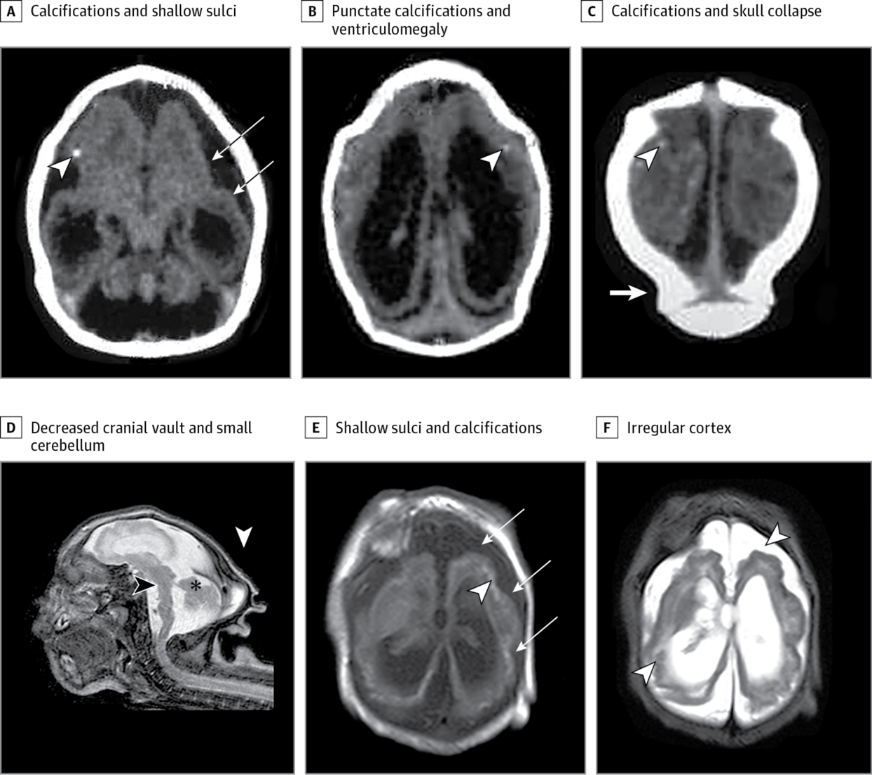

1. Đầu nhỏ nặng (>3 SD dưới ngưỡng trung bình), tìm thấy những đặc điểm gợi ý về tổn thương não bộ của trẻ bao gồm: hộp sọ bị sụp 1 phần, các đường khớp sọ chồng lên nhau, xương chẩm nhô cao, da đầu dư thừa và suy giảm chức năng thần kinh.

2. Não biến đổi bất thường: vỏ não mỏng với những nếp nhăn bất thường, tăng những khoảng chứa dịch, vôi hóa dưới vỏ não, bất thường thể chai, giảm lượng chất trắng, và giảm sản thùy nhộng tiểu não. Trong các điểm trên, cần lưu ý đặc biệt tổn thương vôi hóa dưới vỏ não là điển hình của hội chứng Zika bẩm sinh, nó khác với tình trạng vôi hóa quanh não thất khi bị tổn thương não bẩm sinh do CMV (Cytomegalovirus).